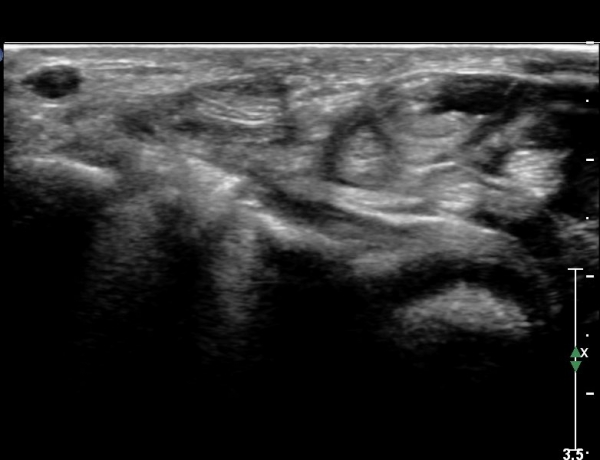

ÃÊÀ½ÆÄ ¼Ò°ß

¾Æ·§ÆÈ »óºÎ Ⱦ´Ü¸é°Ë»ç¿¡¼­ Àü°ñ°£ ½Å°æ Áö¹è¸¦ ¹Þ´Â FPL, FDP ¿¡¼­ ½Å°æ¸¶ºñ ¼Ò°ß(°í¿¡ÄÚ ±ÙÀ§Ãà)À»

º¸ÀÌÁö ¾ÊÀ½(»çÁø 1)